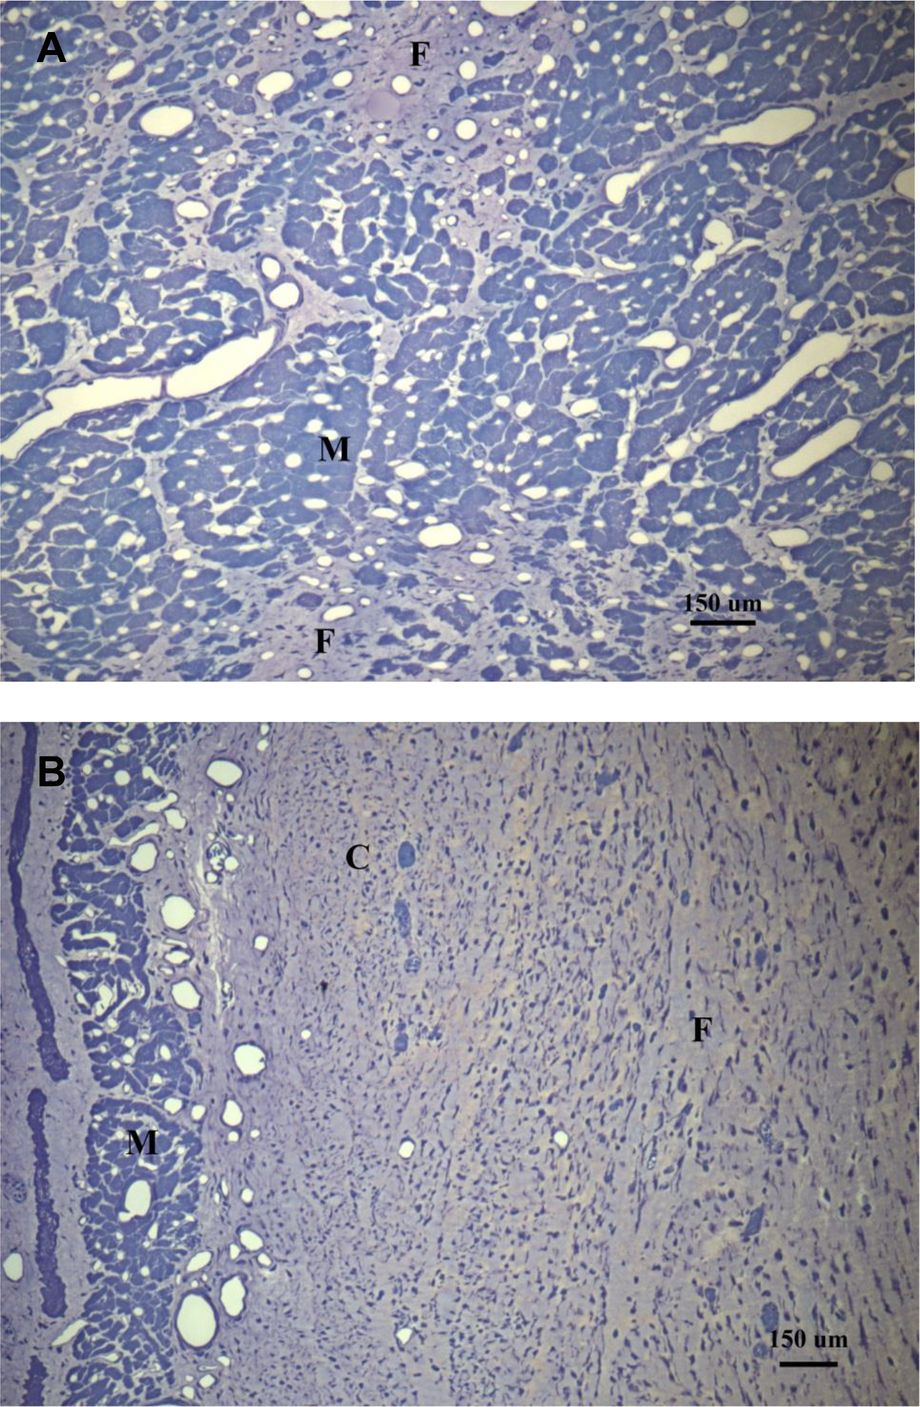

Macroscopic examination of the venous system in the explanted hearts did not show evidence of venous aneurysms or vein degradation. Histological examination of the myocardium in Group I (Figure 6A) demonstrated the absence of edema and hemorrhage after 8 weeks of revascularization. Only small areas of fibrosis and myocyte vacuolization were observed. In Group II (Figure 6B), there were large areas of fibrosis, necrotic tissue and chronic inflammatory infiltrate substituting the myocytes, more evident in the subendocardial region. Cross-sections of the GCV (Supplementary Material) collected two weeks after VPP device implant as preliminary data for this study, showed a completely occluded vein by thrombus formation in the proximal end of the VPP device (opposite to the CVBG), as well as wall thickness of a normal vein compared to a remoded one post VPP device implant.

Figure 6

Histological images from a representative animal from comparative regions in (A) the treated group (toluidine blue at X100) showing patchy areas of fibrosis, and (B) the control group (toluidine blue at X100) where most of the myocytes have been replaced with fibrotic tissue. M, myocytes with vacuolization; F, fibrosis; C, chronic inflammation.

The histological evaluation of the myocardium revealed small (patchy) areas of fibrosis and regions of myocyte vacuolization in the treated and control groups. These areas of myocyte vacuolization reflect the loss of sarcomeres due to chronic ischemia but are considered hibernating myocardium susceptible to functional recovery upon revascularization, as new sarcomeres repopulate these areas (23). Hochberg and colleagues (24) have previously demonstrated that flow through CVBG perfuses all three layers of the myocardium, but most importantly the subendocardium (Figure 6A), the most vulnerable layer to ischemia/infarction in the absence of flow (Figure 6B).